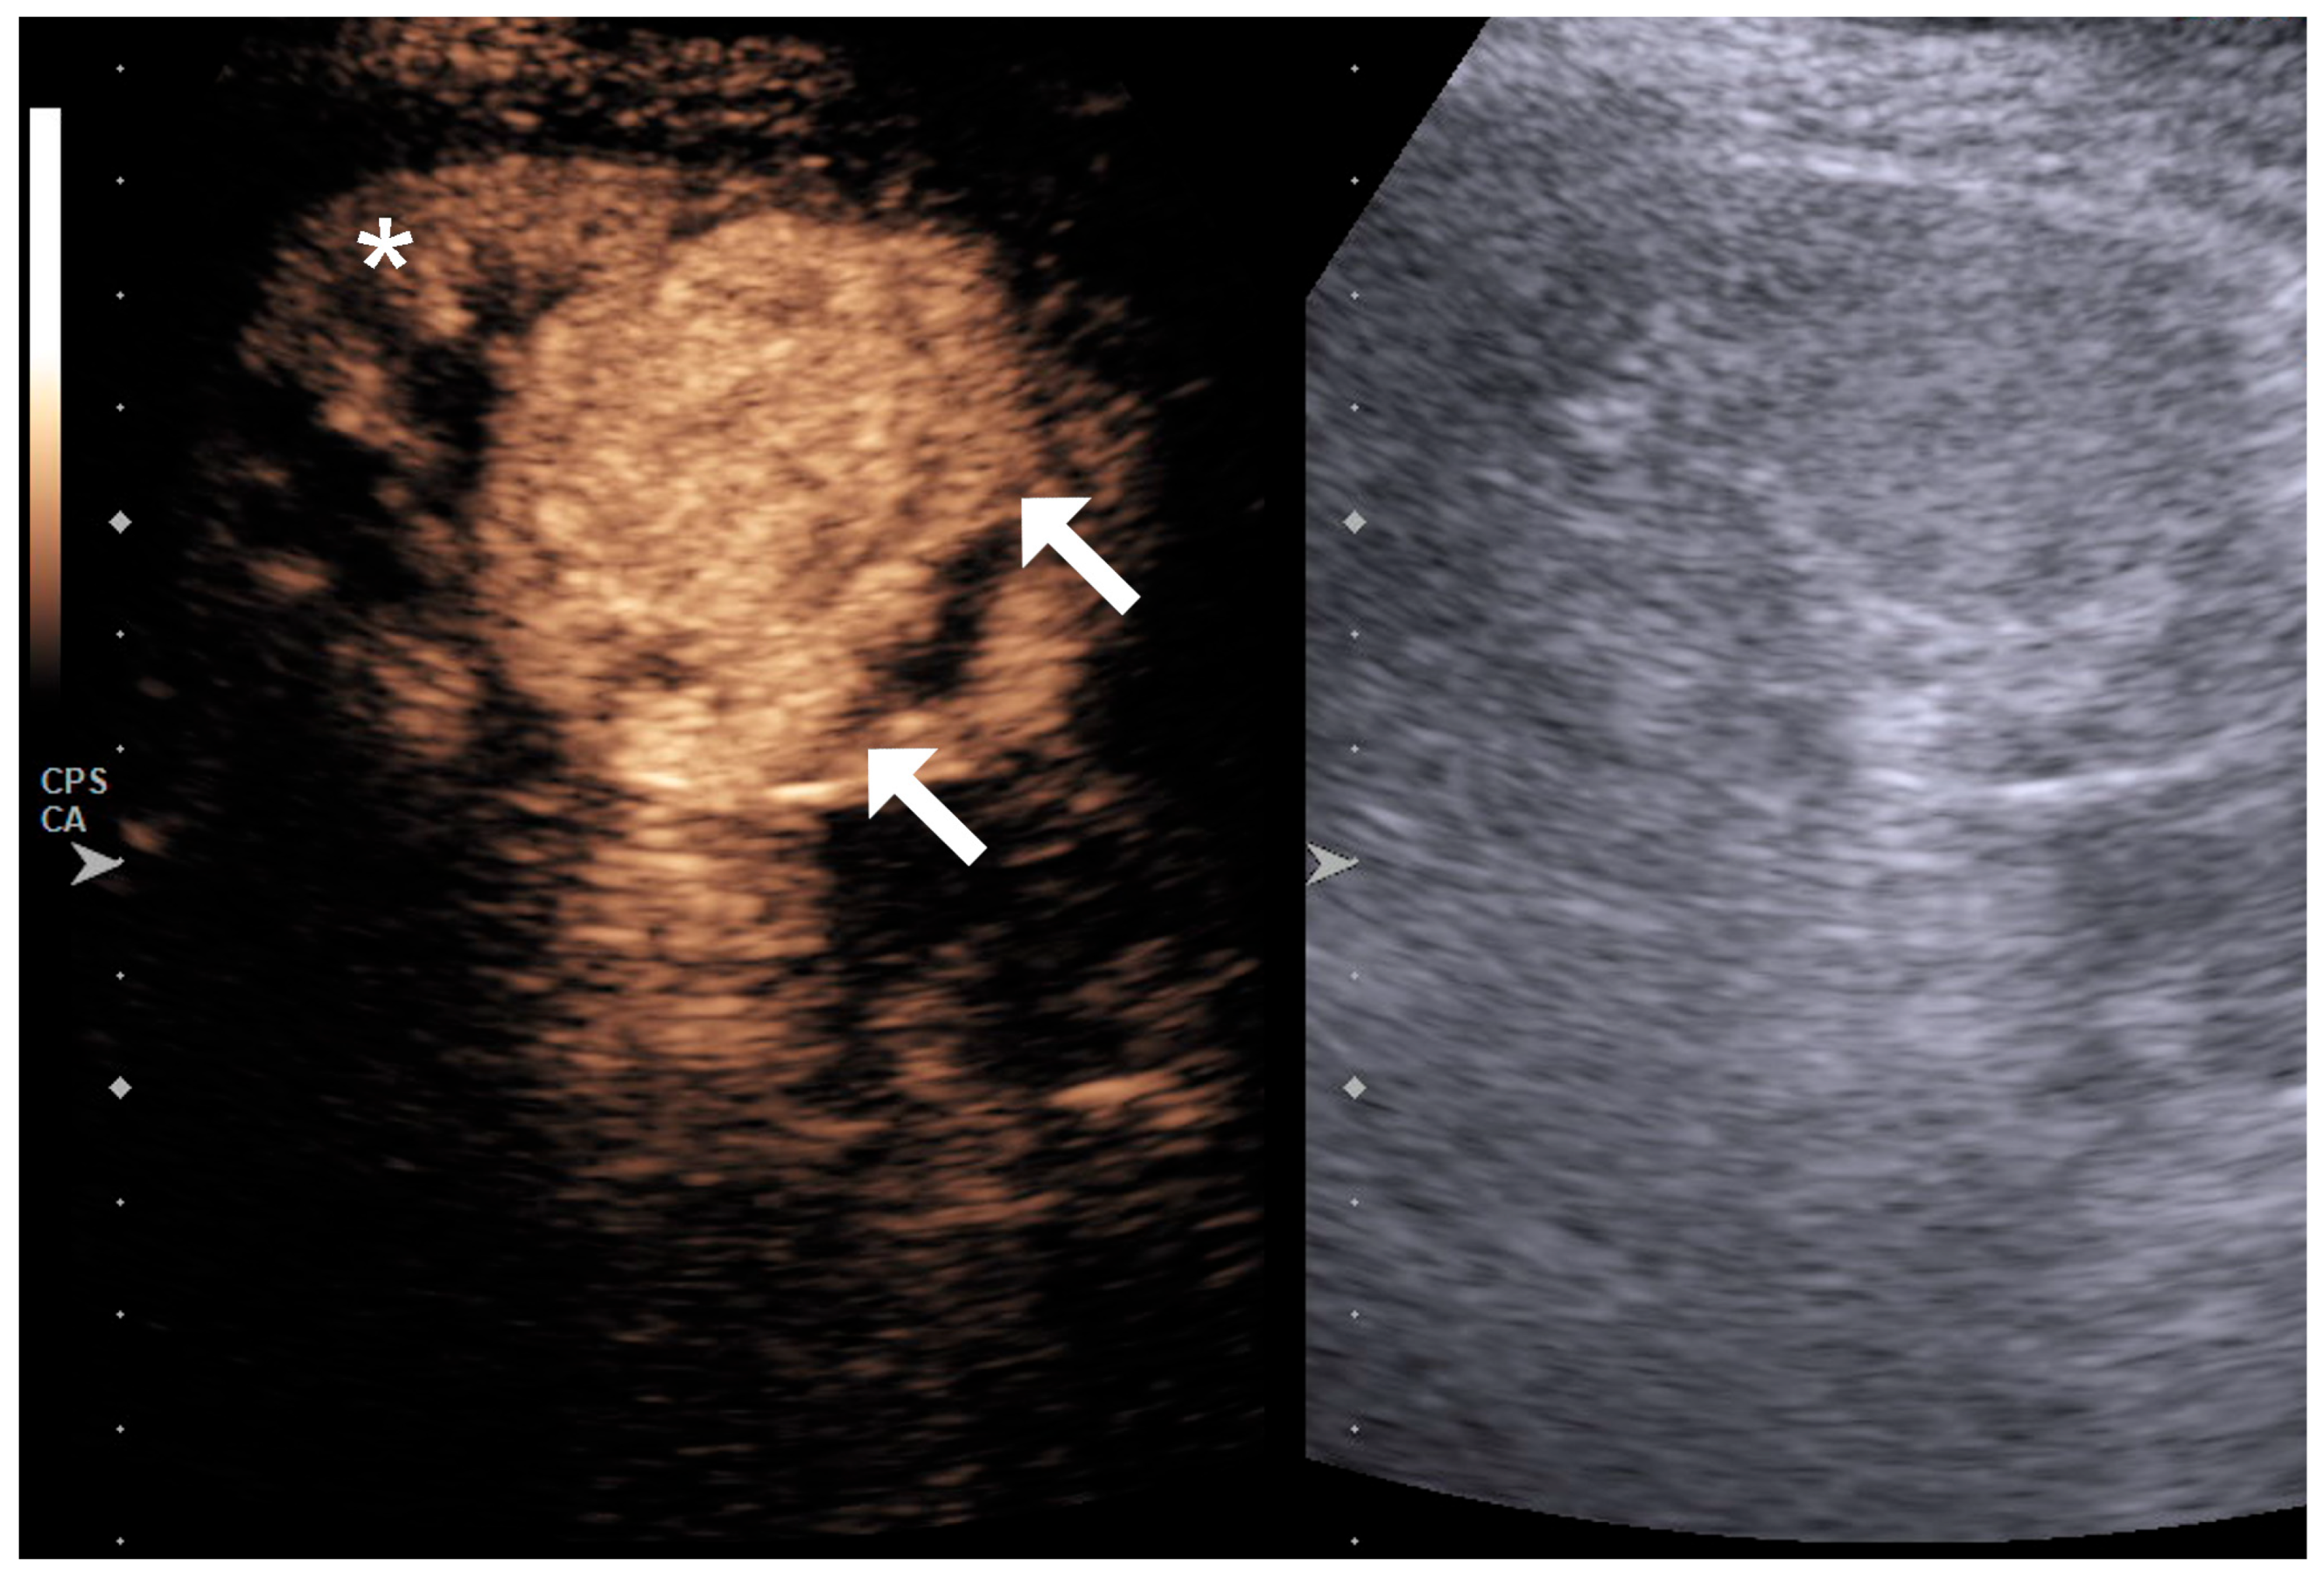

2.2. Image Acquisition and Analysis

4.1. Qualitative Evaluation